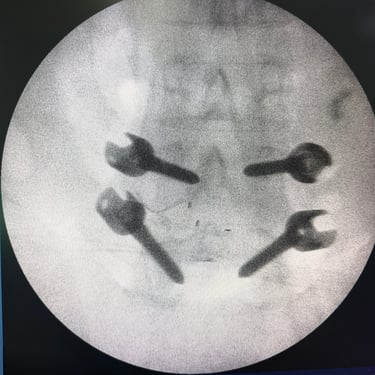

Listesis Lumbar: Artrodesis con Tornillos Transpediculares y Fusión Intersomática Transforaminal (TLIF).

La listesis lumbar es el deslizamiento anormal de una vértebra sobre otra, lo que puede generar dolor lumbar crónico, inestabilidad y compresión de las raíces nerviosas. Cuando el tratamiento conservador no es suficiente, la artrodesis con tornillos transpediculares (FTP) asociada a la fusión intersomática transforaminal (TLIF) es una técnica quirúrgica efectiva. Este procedimiento permite estabilizar la columna, restaurar la alineación vertebral y lograr una fusión sólida, al mismo tiempo que descomprime las estructuras nerviosas. La combinación de estas técnicas mejora el control del dolor, la función neurológica y la calidad de vida del paciente.